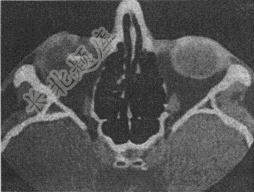

- 单项选择题一23岁患者,CT扫描结果如图所示

该患者可诊断为 A、左眼玻璃体内异物

B、左眼球壁异物

C、右眼球壁异物

D、右眼玻璃体内异物

E、正常眼球结构